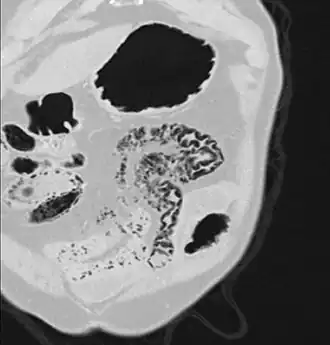

Pneumatosis intestinalis in computed tomography with intestinal ischemia. Lung window for better representation of the gas deposits in the intestinal walls. -